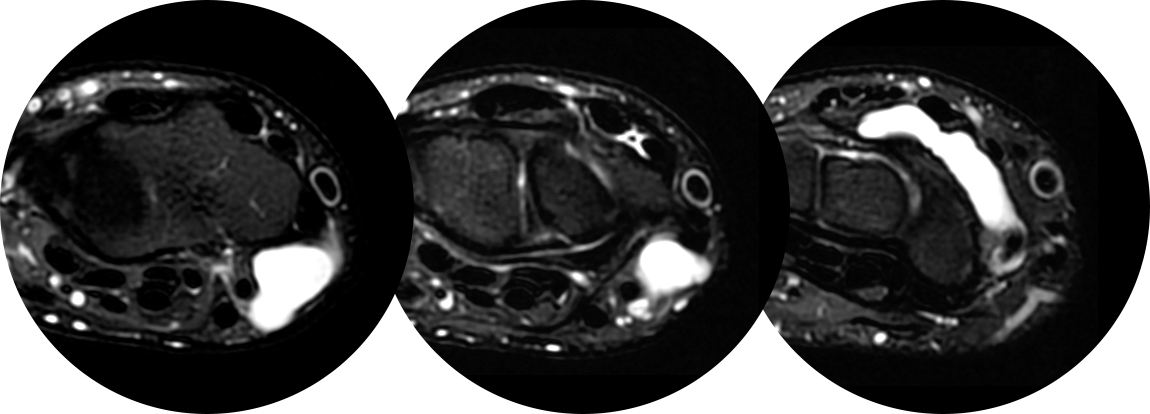

손목 앞쪽의 결절종이 있었지만, 뿌리는 손등쪽하고 연결된 까다로운 경우의 MRI 입니다.

만약 MRI 를 찍지 않았다면 손목 앞쪽에 보이는 결절종만 제거하여 재발 가능성이 높을 수 있는 경우입니다.

이 환자의 경우 앞, 뒤에 절개를 넣어 뿌리까지 제거해주어 재발 없이 유지되었습니다.